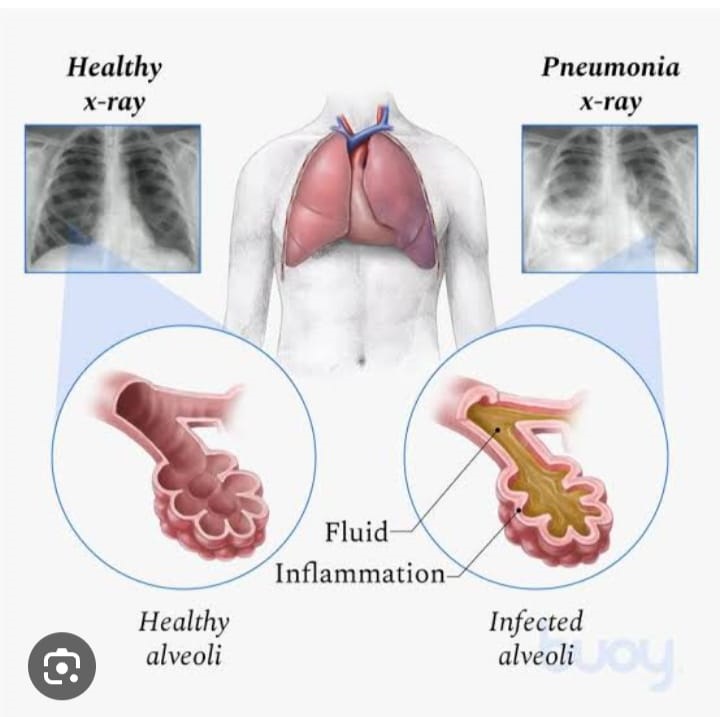

A lung infection is a condition in which a disease-causing microorganism causes damage and inflammation—due to the gathering of immune cells—in the airways or tissues of the lungs.

Lung infections can be mild or severe and can affect people of any age—though some infections are much more common at certain ages. They may affect airways of any size (bronchi, bronchioles, alveoli) or the tissues that surround the airways of the lungs.

VIRAL &BACTERIAL PNEUMONIA